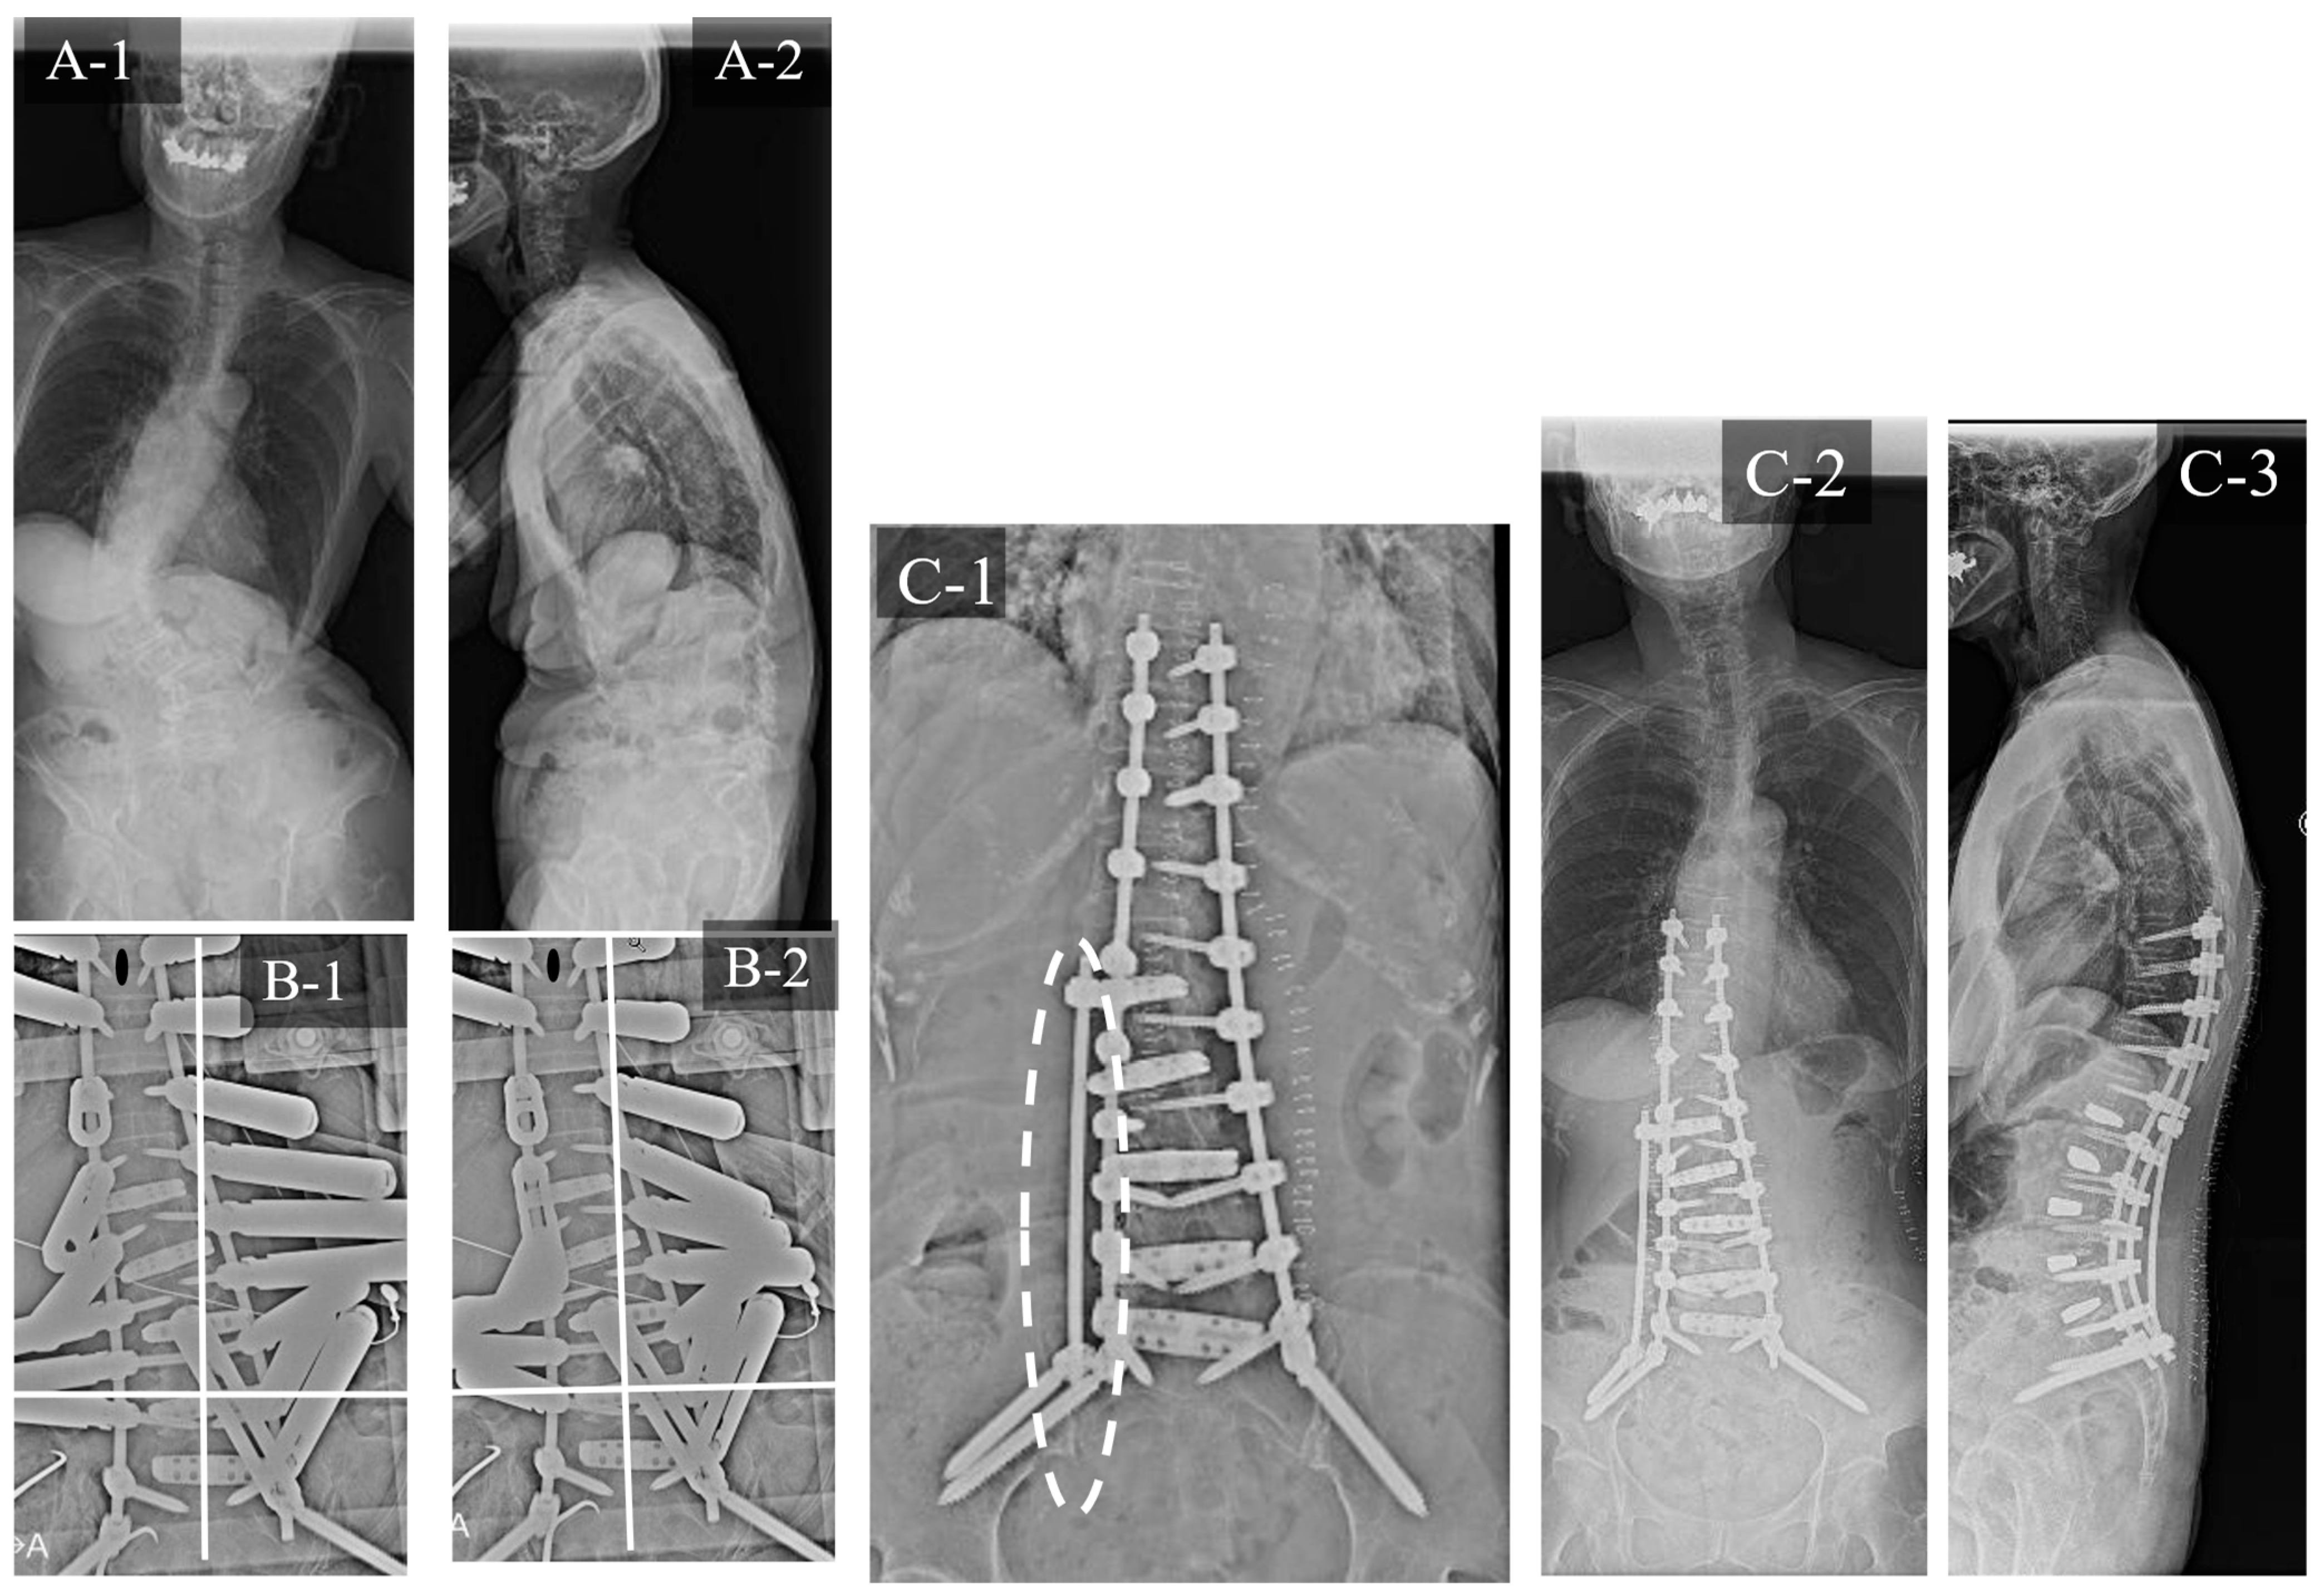

3.3. Case Study 3: RR and KR